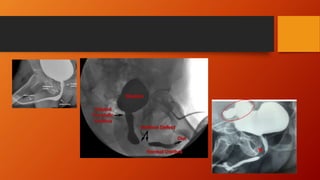

Urethral stricture